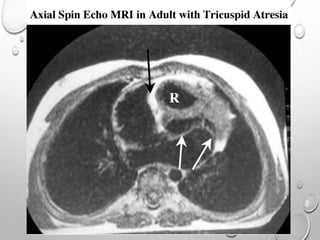

Magnetic resonance imaging (MRI) and computed tomography

(CT) scan

with modified Fontan repair. The Fontan conduit (white arrow) runs from th

atrium (A) around the front of the heart towards the pulmonary artery. Note

front of the heart is identified by the anterior atrioventricular sulcus tissue

containing the signal void of the right coronary artery (black arrow

OTHER LABORATORY STUDIES Pulseoximeter and blood gas values are useful in quantitating the degree of hypoxemia, thereby indicating the severity of pulmonary oligemia. Hemoglobin and hematocrit values are useful in children; the degree of polycythemia is useful in estimating the severity of hypoxemia. Magnetic resonance imaging (MRI) and computed tomography (CT) scan

with modified Fontanrepair. The Fontan conduit (white arrow) runs from th atrium (A) around the front of the heart towards the pulmonary artery. Note front of the heart is identified by the anterior atrioventricular sulcus tissue containing the signal void of the right coronary artery (black arrow